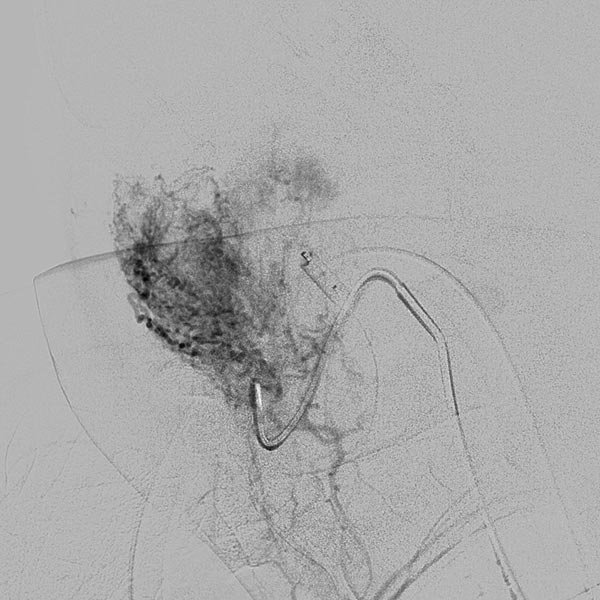

Digitale Subtraktionsangiographie (DSA): Nach Einbringen transarteriell eines Führungskatheters 4F in die Arteria carotis externa und Vorbringen eines Mikrokatheters in die Arteria maxillaris. Das Hämangiom zeigt sich als typisches KM-Pooling (Tumorblush). Gut zu sehen auch der transvenös eingebrachte Ballon, der den venösen Abstrom ausblockt. Hier wird jetzt mit Partikeln der Größe 150 Mikron embolisiert ohne dass diese Partikel venös abströmen können.